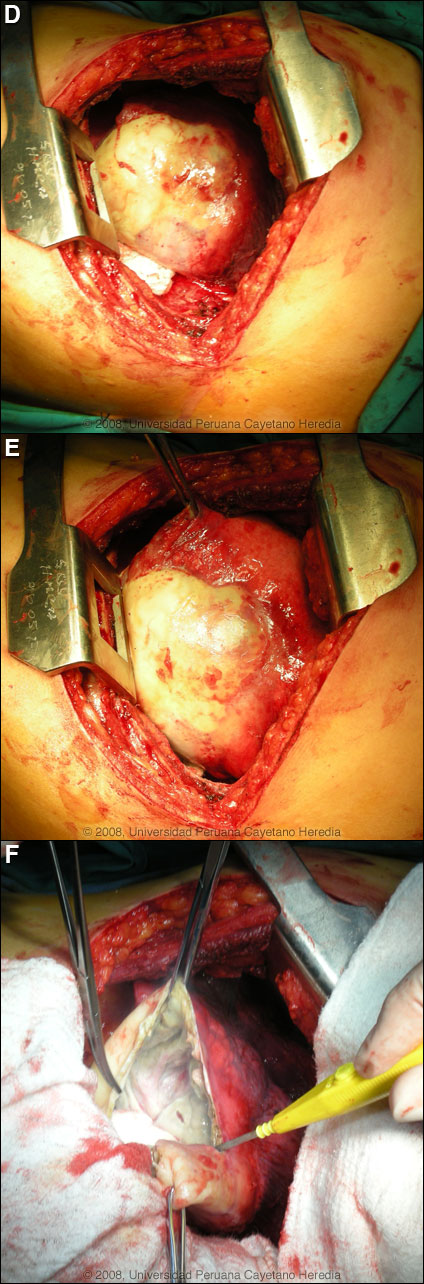

Epidemiology: The patient is a lifelong resident of the Andean highlands around Abancay. He is an anthropologist who travels extensively across the country. No history of or known exposure to TB. No ingestion of uncooked food. Physical Examination: Afebrile, respiratory rate 29, pulse: 100, BP: 100/60. Decreased breath sounds with dullness in the left lower lung, diffuse rhonchi with wheezing. No hepatosplenomegaly. A diffuse erythematous rash was present diffusely. Laboratory Examination: Chest X-ray 1 week prior to acute deterioration [Image A] and computer reconstructed view [Image B] from a CT scan performed at the same time. A CT scan just after admission is shown in Image C. Hematocrit: 44%, WBC: 17,000 (94 neutrophils, 1 eosinophils, 1 basofils, 2 monos, 4 lymphs), 317,000 platelets. Sputum AFB negative. Normal liver function tests and abdominal ultrasound was normal. A diagnostic procedure was performed.

![]() Discussion: A Western Blot taken before the acute rupture was strongly positive for E. granulosus. The expectoration of large amounts of salty fluid is highly characteristic of this catastrophic event. The 2nd CT scan showed no pleural fluid indicating erosion and rupture of the cyst only into the bronchus. The elevated peripheral WBC is likely indicative of some bacterial superinfection post-rupture. Human hydatid disease secondary to Echinococcus granulosus is caused by the larval form of this dog tapeworm. Humans ingest the tapeworm eggs in environments contaminated by canine feces and become accidental intermediate hosts. Sheep are the normal intermediate hosts. Larval cysts expand slowly over years or decades becoming symptomatic as they impinge on other structures by virtue of their size. Spontaneous cyst rupture as occurred here happens in the minority of cases but is not rare. The cysts contain hundreds of viable scoleces capable of becoming adult tapeworms upon ingestion by a definitive host such as the dog. The internal germinal membrane lining the cyst produces new scoleces on an ongoing basis. Each scolex is capable of becoming a new daughter cyst either within the original cyst or elsewhere should the original cyst rupture or be ruptured. An example of seeding of the pleural cavity is seen in a previous case of the week (Gorgas Case 2005-10). Hydatid disease is common in sheep-raising areas worldwide. Most primary infections involve a single cyst. 65% of solitary cysts are found in liver, 25% in lung and the rest in a wide variety of other organs including kidney, spleen, heart, bone and brain. In patients with a pulmonary cyst, approximately 15% will also have a hepatic cyst. Serology is usually positive with hepatic cysts but sensitivity drops below 50% with solitary pulmonary cysts even when the cyst is large. With the large burden of disease in this patient’s lung a positive serology would be expected. Praziquantel is the most potent scolicidal drug and is the drug of choice for all adult tapeworms. However, praziquantel cannot penetrate the hydatid cyst wall so is only useful as an acute therapy when a cyst ruptures (spontaneously or due to surgical mishap) and scoleces are lying free before encysting again. Albendazole is the therapy of choice for intact cysts that are not operable, such as when there are multiple or diseminated cysts. A trial of Albendazole may also be considered for solitary cysts that are less than about 10 cm. Response is generally slow and only complete in a minority of cases. Surgical resection is the therapy of choice for large intact solitary cysts and certainly in a case like this with an acute rupture and a broncial-cyst fistula. At thoracotomy, the cyst was found to be intact on all surfaces within the lung parenchyma and was flaccid with little remaining fluid indicating that fortunately no fluid (which would contain protoscoleces) [Images D, E] had escaped into the pleural space. Unfortunately, the outer membranes were highly adherent to the lung parenchyma precluding shelling out and removal of the cyst alone and necessitating a left lower lobectomy. Image F shows the inner or germinal membrane that lines the cyst and that is responsible for the ongoing generation of new protoscoleces as the cyst grows in size. Perioperative Albendazole in case of cyst rupture during the procedure is frequently utilized for hepatic cysts even though scolididal agents are always injected into the cyst intraoperatively before any resection is attempted. In the case of pulmonary cysts most surgeons feel that cyst softening that may occur with albendazole makes the operative procedure more complicated and increases the risk of rupture at the time of resection.